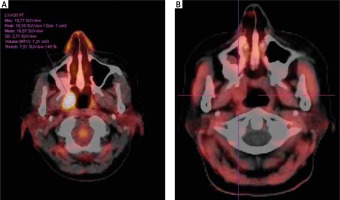

Fig. 4

Patient no. 32. A) Solitary myeloma lesion suspected in the right palatine tonsil, positive in FDG PET/CT, showing high uptake SUVmax 18.77. B) Negative FET PET/CT result showing no tracer uptake in the right tonsil. No subsequent clinical progression of myeloma was observed on further follow-up